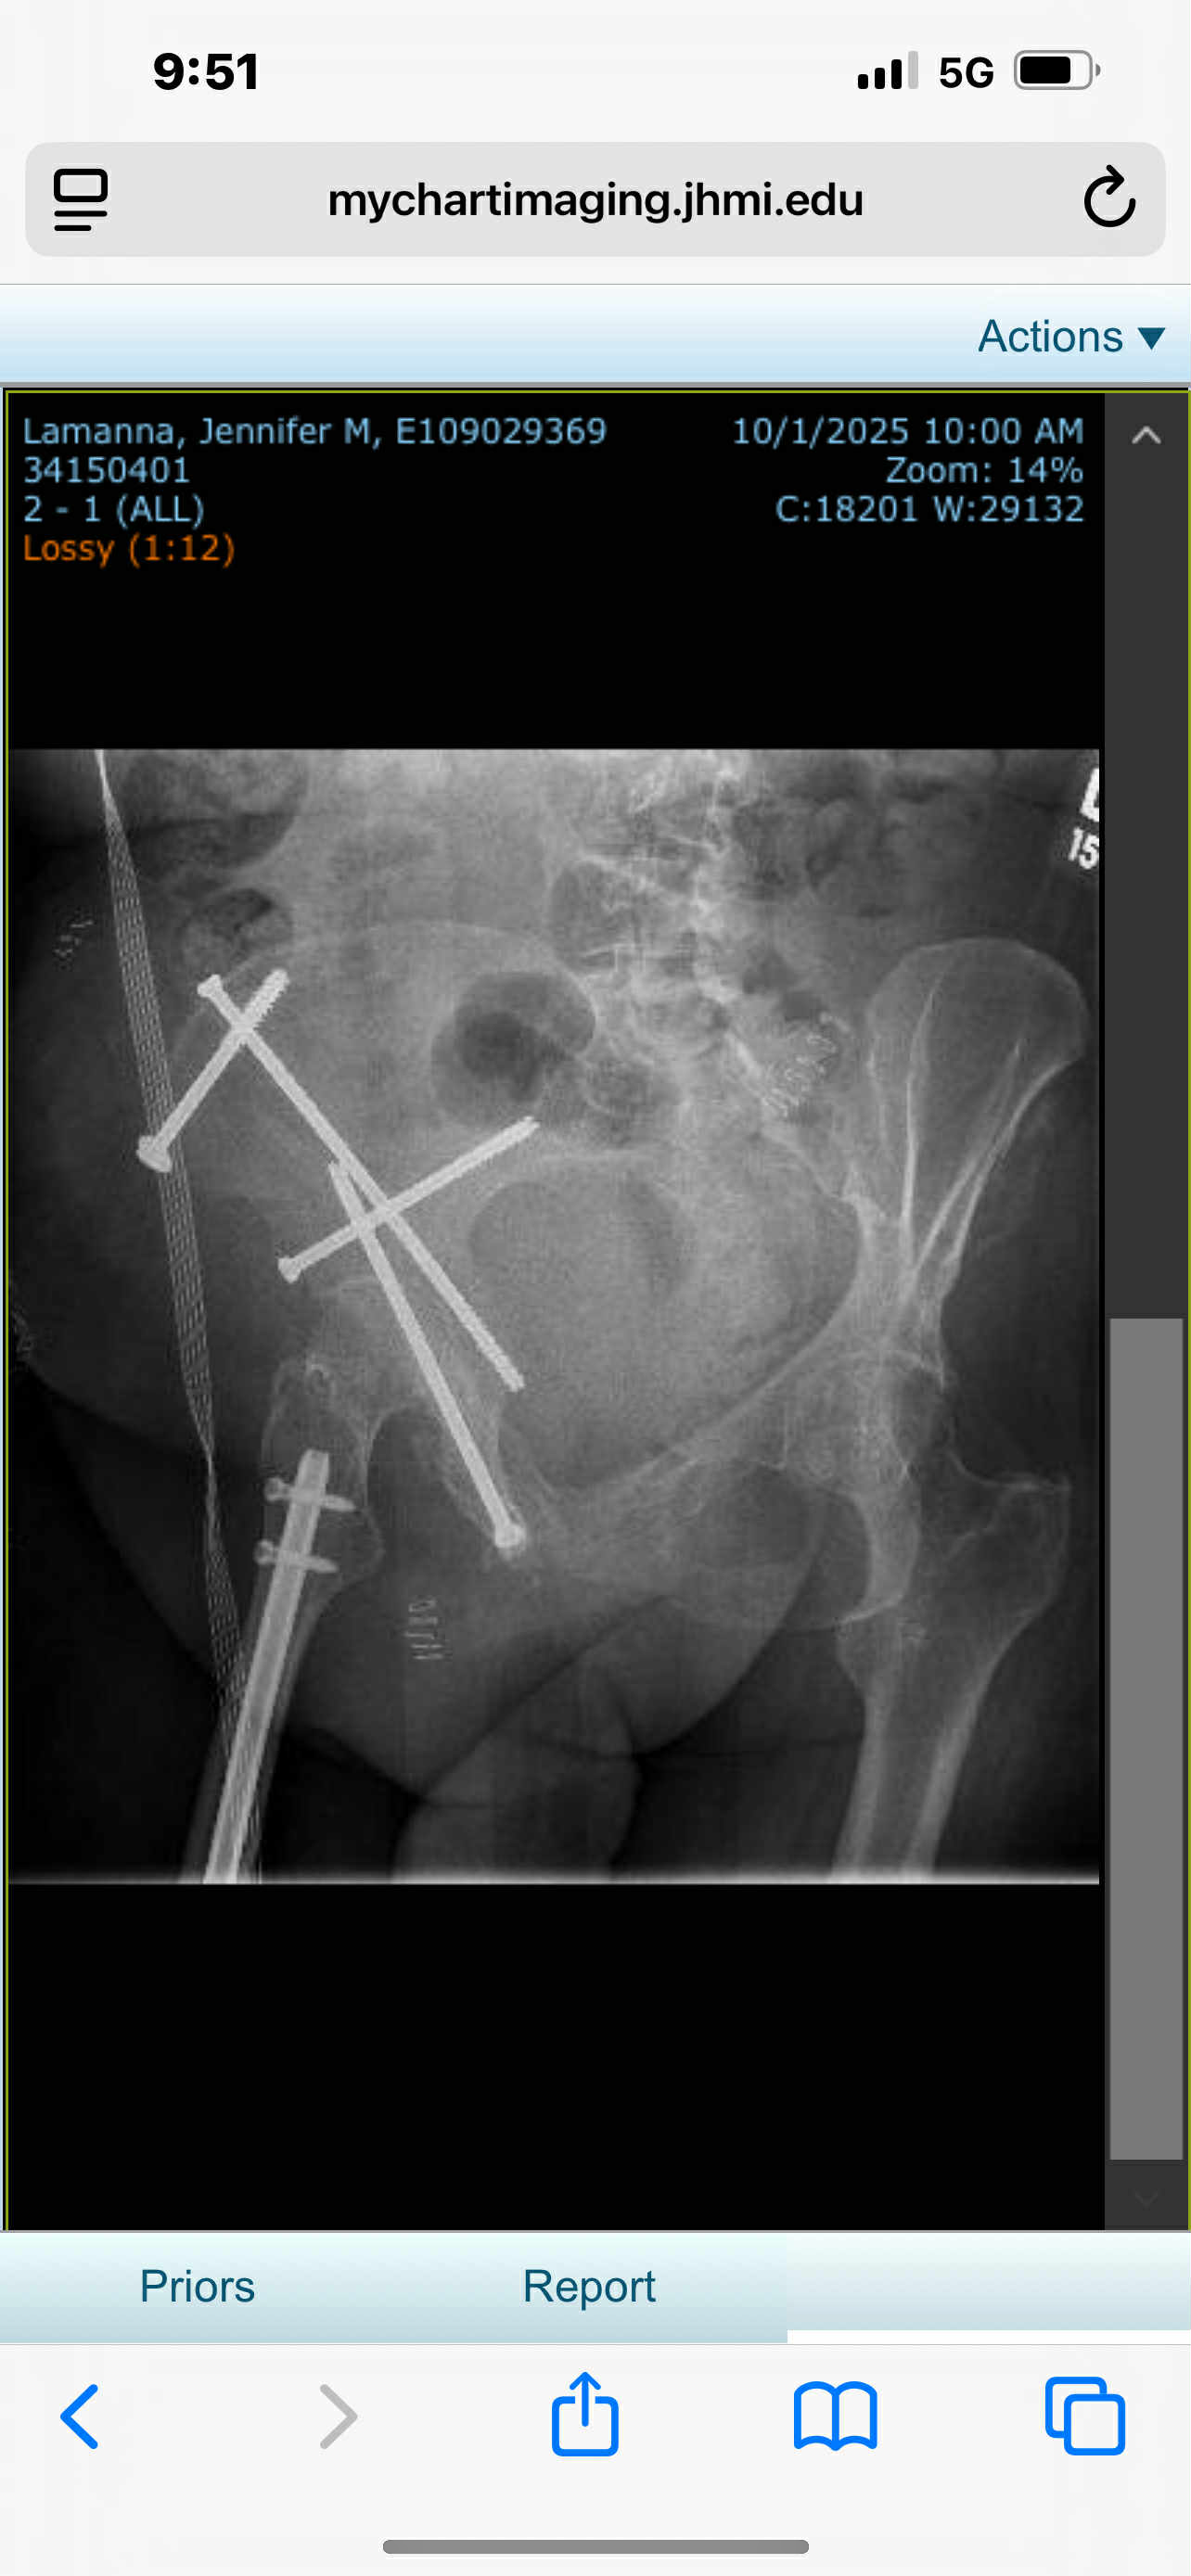

I am sure many of you remember Boris and many of you were part of his success story in 2000 when we treated him for 321 days and were able to beat FIP for him. He just turned five this year. Last month we have run into some issues medically for myself where on September 27 I sustained a fall in our house and I broke my right pelvis and I had surgery on September 30th. I was discharged on October 9 and then on Sunday the 12th Boris was having trouble breathing and we had to take him to the Pet ER hospital. He was admitted and had a bunch of fluid tapped from his chest and a bunch of diagnostics ran, including a lot of heart exams, which thankfully all came back clear, but unfortunately leaves a relapse of FIP as his diagnosis. He has been in the pet hospital since Monday and our current bill there is over $10,000 right now and we are approaching maximum tap out on all of the credit sources that we have. With me having to struggle to recuperate from this broken pelvis a lot of this care has fallen on my husband‘s shoulders and we are both having a very difficult time. We were able to order the GS drug for Boris and we started him on October 14 but unfortunately, it is taking quite a while to kick in and he has had to have fluid tapped from his chest five times now, which has resulted in having chest tubes put in today the 18th. We also upon advice with our original FIP team have started him on a second line medicine of Paxlovid and the hospital will be starting him on that this evening. This is a Hail Mary for him. If the paxlovid does not come through then we are going to have to make some really difficult decisions in the next week. I’m reluctantly turning to you for more help with him because financially this is really putting our family into a bind, and I am humbling requesting any amount that you could possibly donate toward his care and his bills because it would really help with all of the stress that we are both under.

i’ve uploaded a picture of the x-ray showing the metal that was implanted into my pelvis to give an idea of the type of surgery that I am trying to recuperate from. I’ve also uploaded one of the bills showing a running total at the Pet ER hospital to be over $10,000. This does not include the cost of the cardiac testing which was close to 8000 or the GS medicine which was 1200 or the cost of the paxlovid which was 1500. We’re going to have more costs coming in for him, regardless of the decisions that we might have to make in the next week for him - whether it’s more time treating him or having to let our sweet boy go.